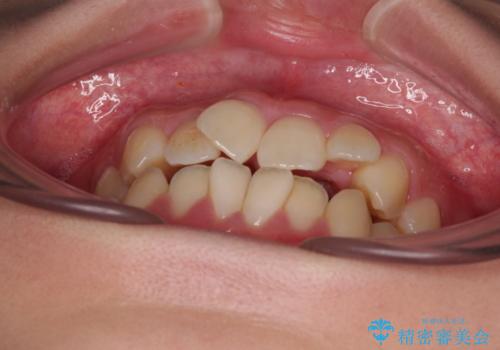

- 前歯のデコボコと唇の閉じにくさを気にして来院された患者様です。

単純に上下左右の第一小臼歯4本を抜歯して口元の突出感を改善することも考えられましたが、上顎骨よりも下顎骨の幅が広いため、より良い咬み合わせを達成することを目的として、急速拡大装置を用いて上顎骨を拡大することとしました。

歯列矯正では基本的に骨格を改善することはできませんが、急速拡大装置(MARPE)を使用することで上顎骨を側方に拡大させることができ、咬合状態を大きく改善することができます。